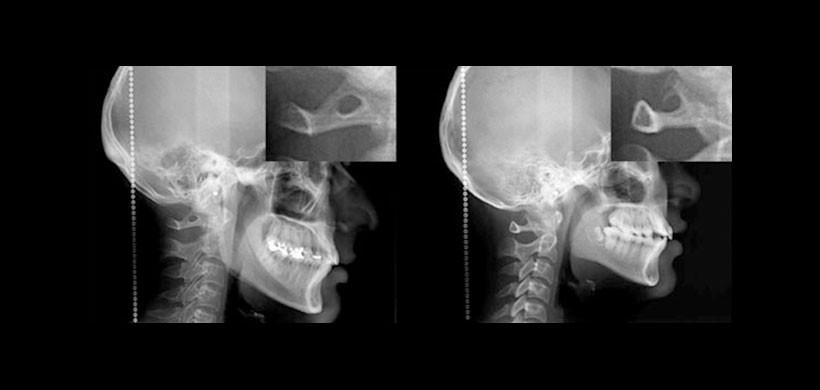

Figura 2. Presencia de ponticulus posticus en radiografías cefalométricas. En la imagen izquierda se observó un puente óseo completo mientras que la imagen derecha mostraba una osificación parcial.